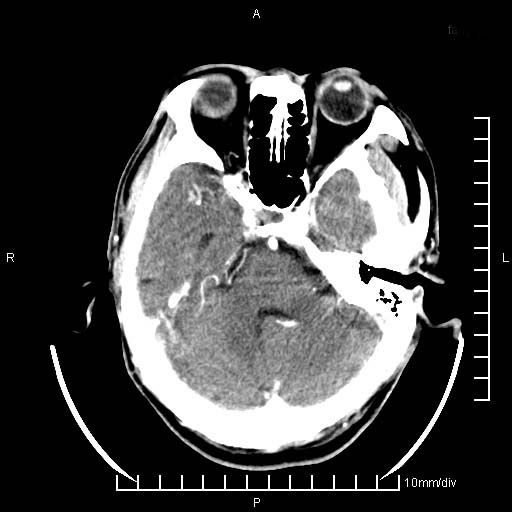

临床以双下肢浮肿,疼痛收治,无明显神经系统症状,既往无梗塞,出血病史。左颞叶见低密度灶,考虑什么?

考虑左侧颞叶脑软化灶。

无强化 无占位 软化灶吧

无强化、 无占位、局部脑沟增宽, 软化灶吧。